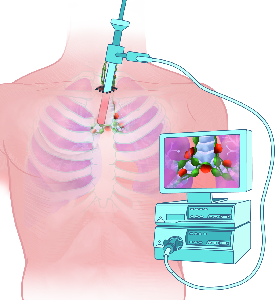

Detailreiche Fotografien aus der medizinischen Praxis ergänzen die Texte; moderne, genaue,

wissenschaftliche Zeichnungen geben Einblick in die Anatomie und die Funktion der Lunge und

anderer Organe.